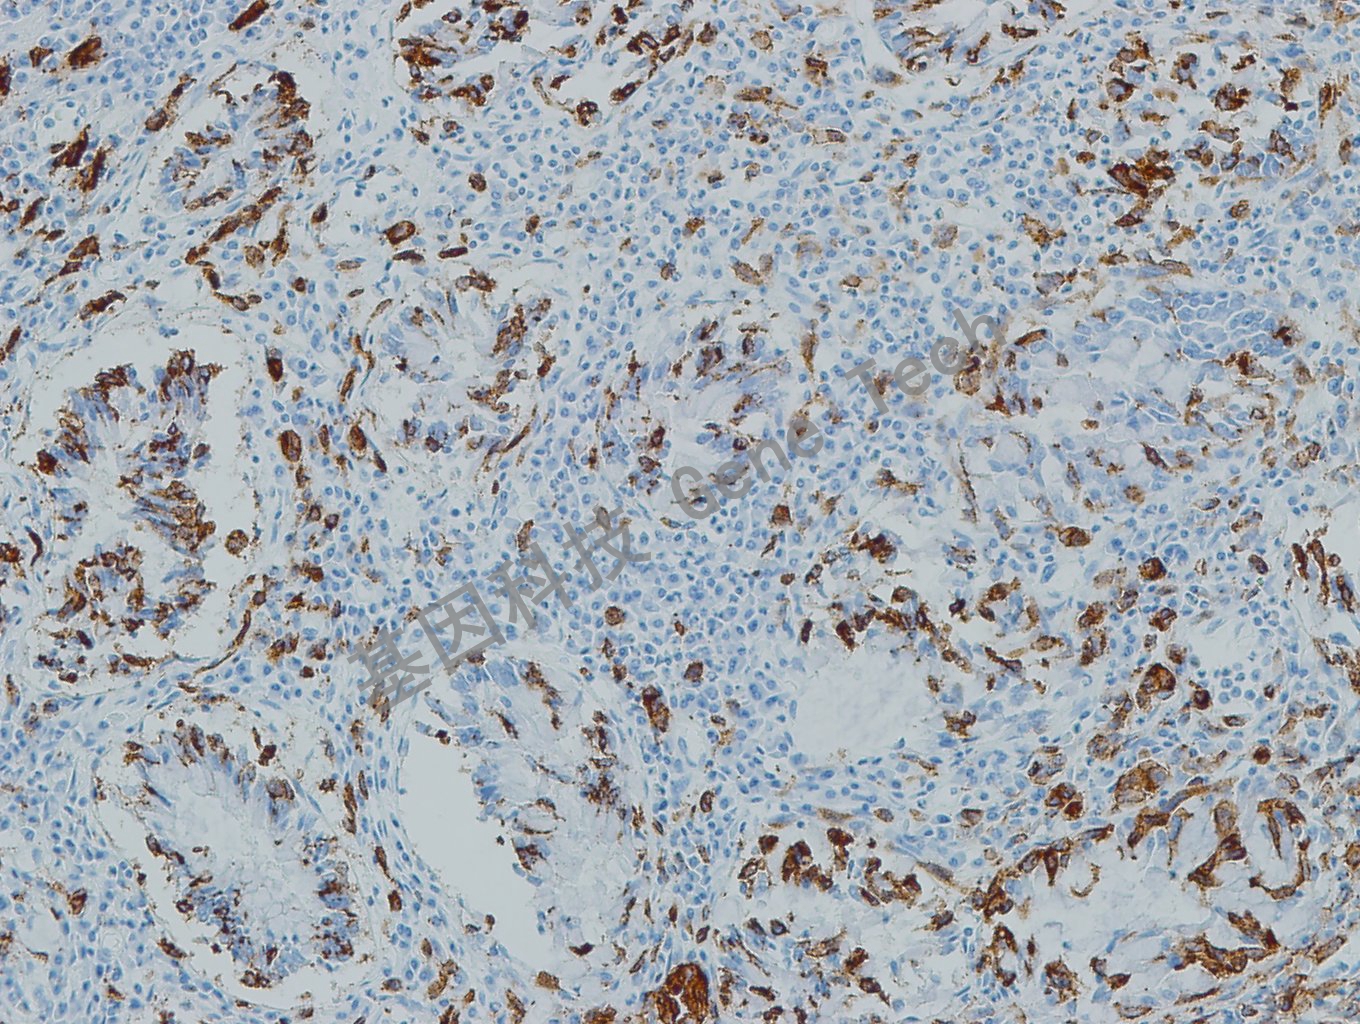

黑色素瘤石蜡切片,用 PNL2(GT2336)染色,细胞浆阳性,DAB 显色。